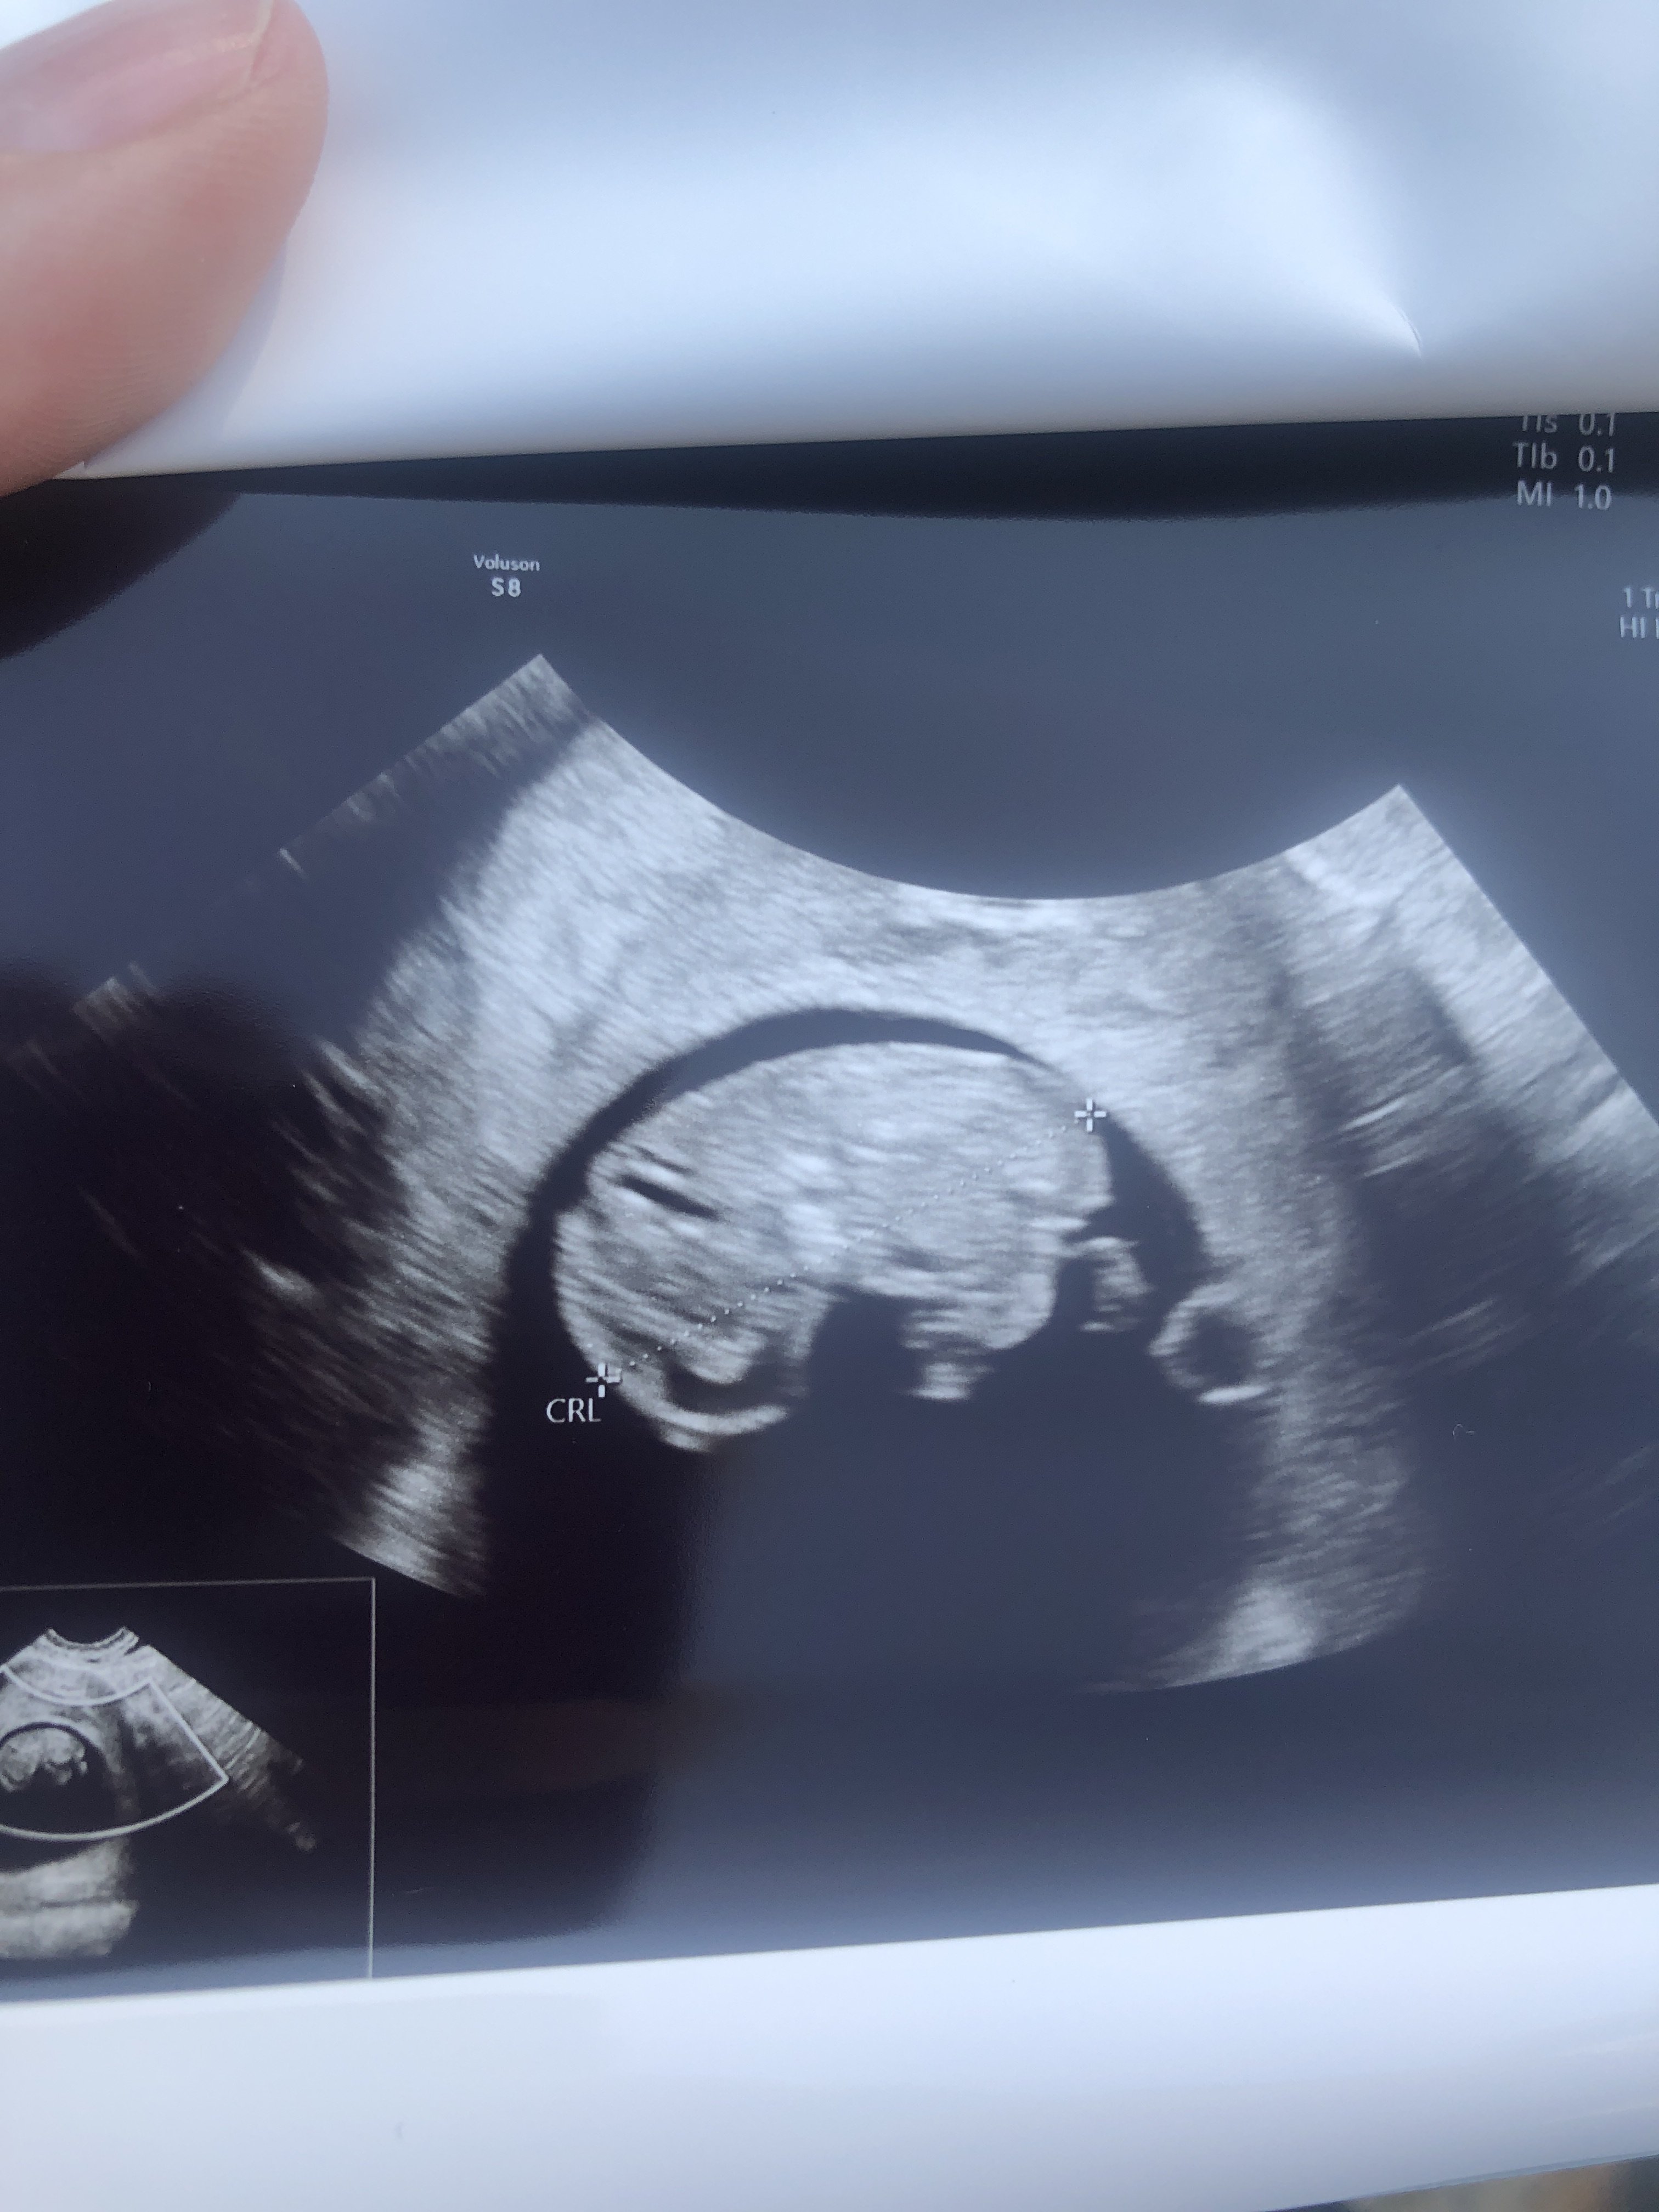

Taki maluszek zdjęcie 9t5dzien 🙂

Załączniki

• 1516D8E3-D4C6-4112-B10C-E7D905A112E5.jpeg

1516D8E3-D4C6-4112-B10C-E7D905A112E5.jpeg

987,6 KB · Wyświetleń: 135